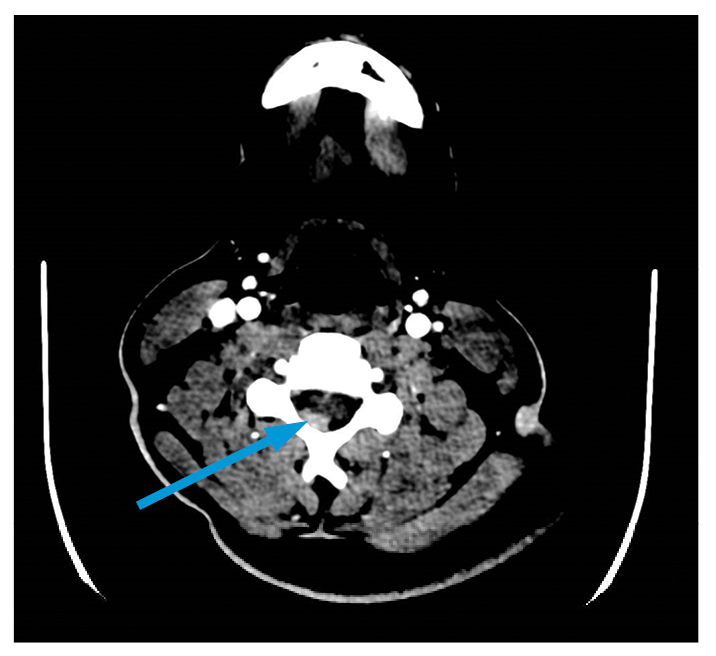

Cyclophosphamide was initiated at 15 mg/kg every 3 weeks for 3 doses. He developed significant and acute testicular pain and a hypertensive emergency (slurred speech and nystagmus). Testicular ultrasound revealed infarction without evidence of torsion, and a computed tomography (CT) scan revealed a hyperdense lesion spanning C4 to C5–6 (Fig. 2), identified on magnetic resonance imaging (MRI) as subarachnoid hemorrhage. The hemorrhage was thought to result from the hypertensive crisis, anticoagulation prophylaxis, or both. Mepolizumab (300 mg SQ monthly) and rituximab (1 g IV twice at 2-week intervals) were added to his induction regimen.

Figure 2: CT angiography of cervical spine with arrow indicating hyperdense focus of right posterior epidural region.